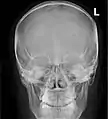

Paranasal sinuses seen in a frontal view

Paranasal sinuses are a group of four paired air-filled spaces that surround the nasal cavity.[1] The maxillary sinuses are located under the eyes; the frontal sinuses are above the eyes; the ethmoidal sinuses are between the eyes and the sphenoidal sinuses are behind the eyes. The sinuses are named for the facial bones and sphenoid bone in which they are located. Their role is disputed and no function has been confirmed.